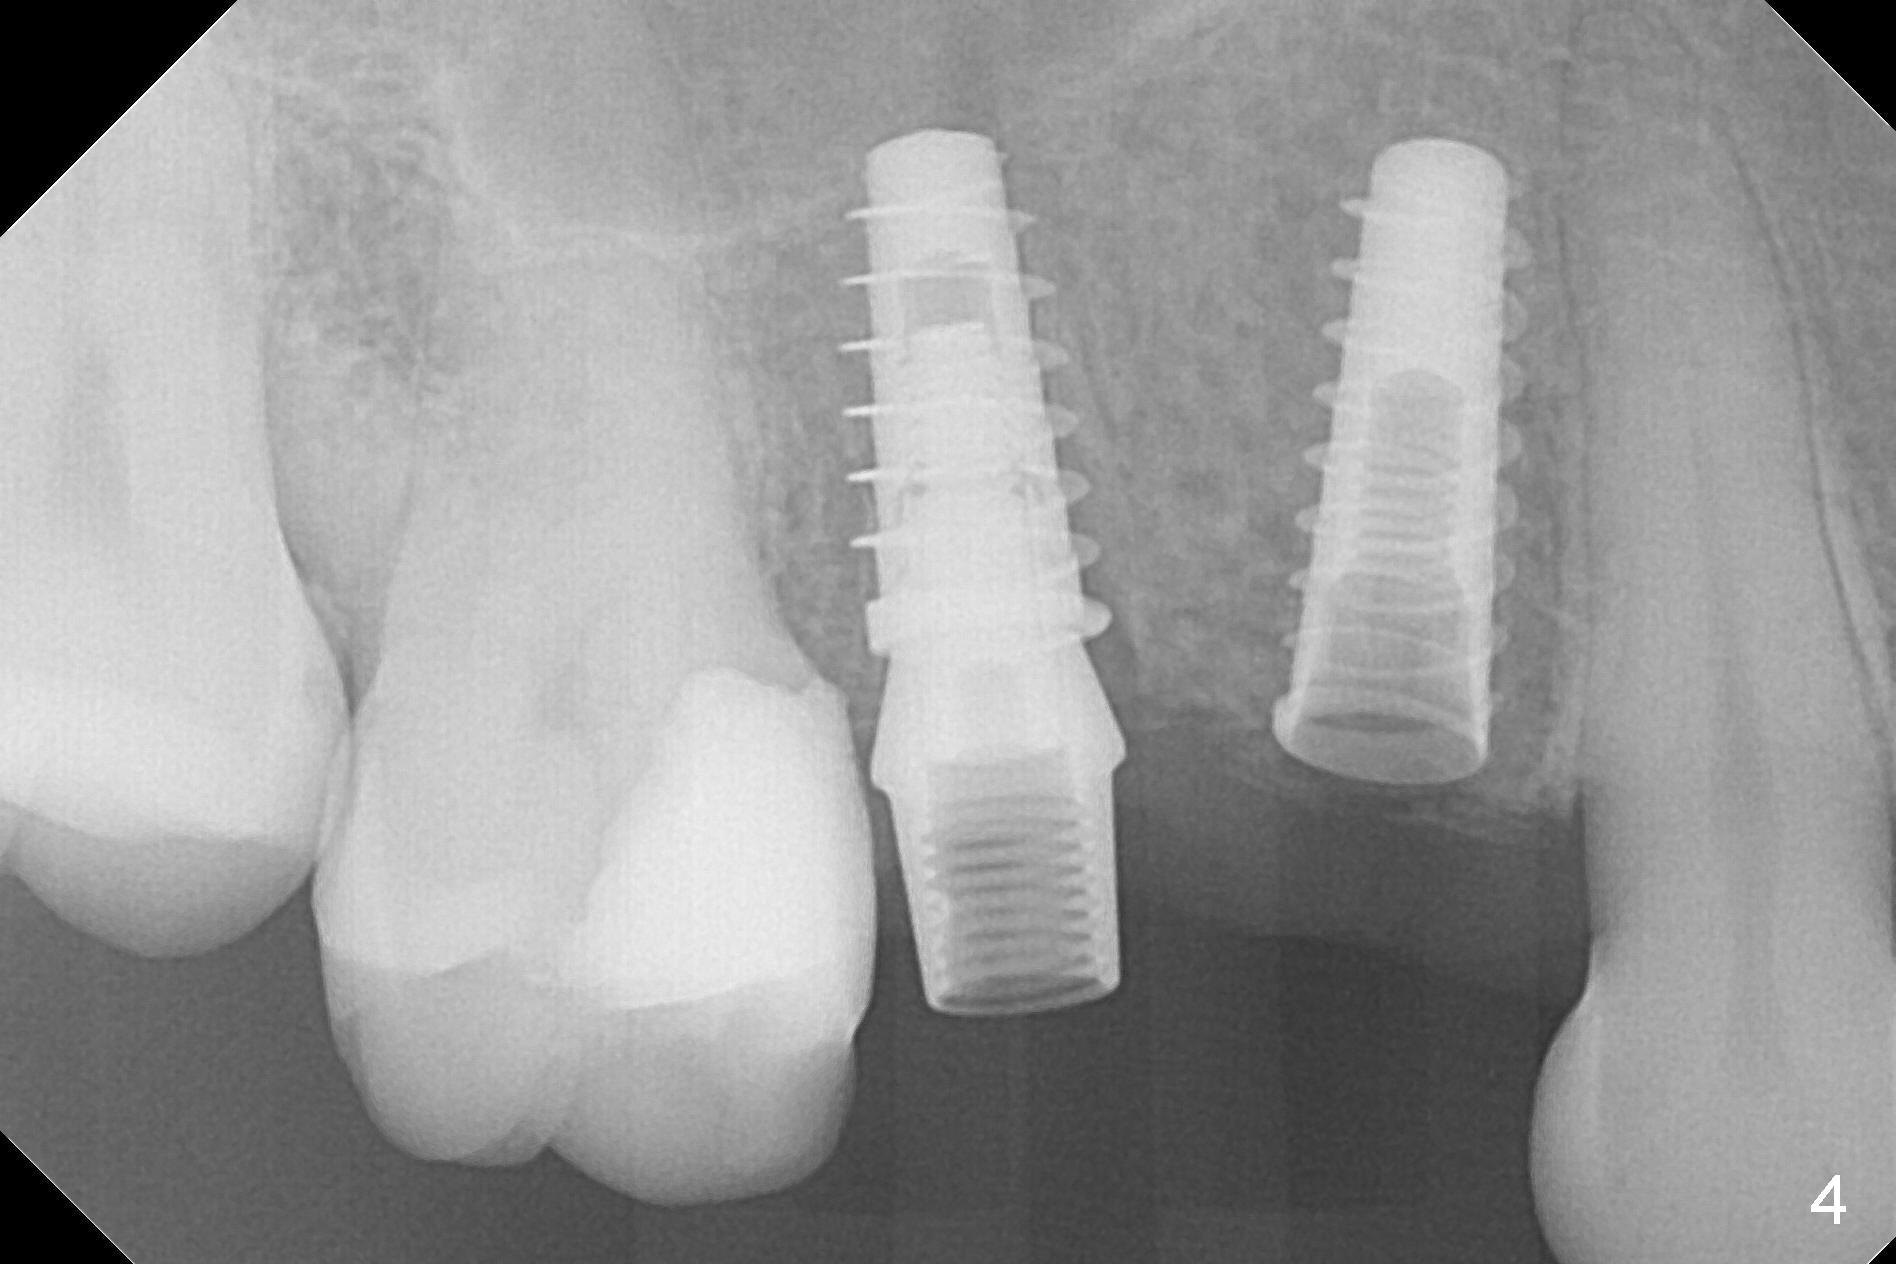

The buccal plate of the socket of #4 is thin and short (Fig.1, 5B (coronal section of the socket) red area) with apical perforation (Fig.5B >). Osteotomy at #4 starts with 1.6 mm drill in the palatal slope (Fig.2 circle; Fig.5C blue arrow), while that at #5 with Magic Split (Fig.2 black line). In fact sinus perforation occurs with the 1.6 mm drill. Osteotomy increases by using Magic Drills sequentially (2.8 and 3.3 mm) at #4 and Magic expander (3.0 mm) and the same Magic Drills at #5 (Fig.3). A 4x11 mm dummy IBS implant is placed with insertion torque of 45 Ncm at #4 with apparently intruding into the sinus (Fig.3). When a 4.5x9 mm implant is placed, the insertion torque is actually reduced (<35 Ncm, Fig.4). As osteotomy or implant diameter enlarges, it shifts buccally with less bone contact buccally (Fig.5D, as compared to Fig.5C)). In brief, once a dummy implant has achieved a reasonably high stability, do not over seat it. A small immediate implant may have more solid bone contact.

At the healed site (#5), insertion torque of a 4x11 mm implant is >50 Ncm (Fig.4). Because of supraeruption of the tooth #28 (Fig.6 arrow), a healing abutment (4x2 mm) is placed at #5 (data not shown), while a pair abutment (4.5x4(2) mm) is placed at #4 (Fig.4,6). In fact a splinted provisional is placed at #4 and 5 with a low occlusal table. There is no apparent bone loss 1 years 5 months postop (Fig.7). In fact the implants either perforate the palaatal or buccal (B) plate, as revealed by CBCT (1 year 6 months postop, immediately post cementation, Fig.8,9). It appears necessary to have guided surgery and smaller implant in the narrow ridge.